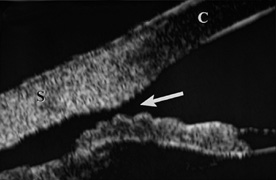

When the cornea is abruptly forced backward by severe blunt trauma, it presses the iris against the lens, preventing the escape of aqueous into the posterior chamber. If enough force is applied, the entrapped aqueous dissects into the ciliary body, resulting in a recessed angle (Fig. 4). This tearing of the ciliary body is responsible for approximately 90% of the hyphemas seen after blunt trauma.31,32 Other causes of hemorrhage include separation of the iris from the ciliary body (iridodialysis) and sphincter tears. Ultrasound biomicroscopy can be useful in diagnosing dissection of the ciliary body or iridodialysis (Fig. 5).33–35

Fig. 5. Ultrasound biomicroscopy image of cyclodialysis (arrow). “C” identifies the cornea, “S” identifies the sclera.